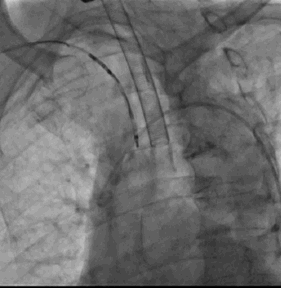

3. 经右侧股静脉置入SL1鞘管,沿鞘管送入房间隔穿刺针,食道超声下见左心耳血栓

4. 超声指导下成功行房间隔穿刺,将鞘管推进至左房后予肝素7000U,SL1 导丝送左房后,超声下测左心耳开口大小后选用LAmbre 左心耳封堵器(20-26mm)